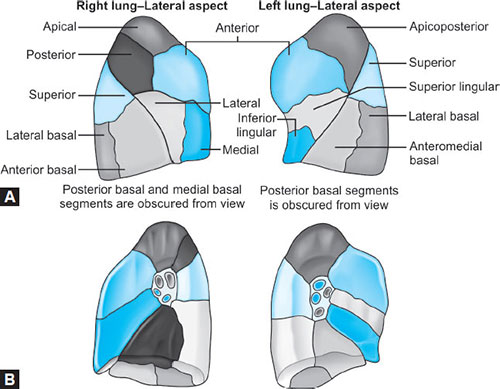

Bronchopulmonary Segments (Figs. 14A and B)